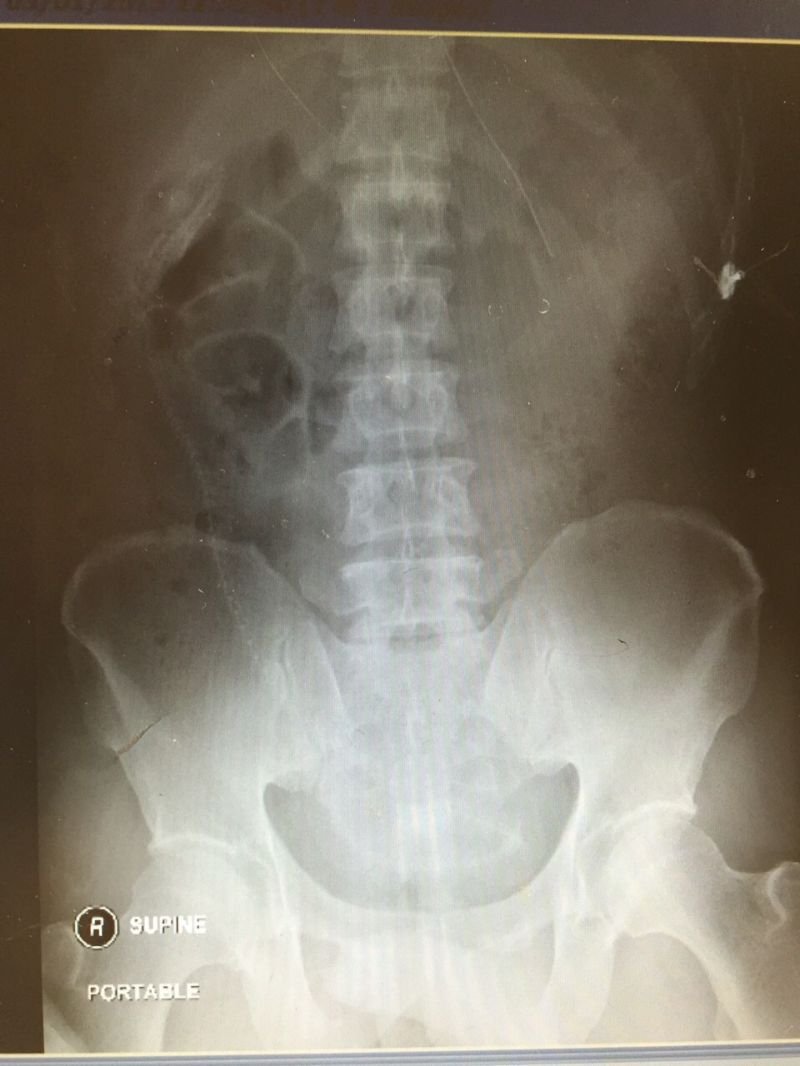

Разгляди на рентгеновском снимке позвоночник угря (18+)

Мужик обратился за помощью в больницу с жалобами на острую боль в кишечнике. Рассказал, что смазал угря лубрикантом и засунул себе в зад, чтобы получить удовольствие. Получил еще какое. Скользкий хвост выскочил из пальцев, и угорь "поплыл", прогрызая кишки на своем пути. В общем, дядьку внутри истерзал серьезно. Жесть.. фу... блуээээ :)